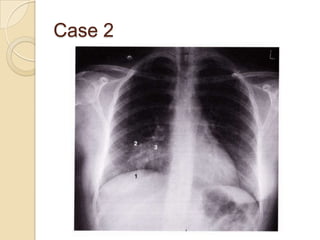

Case 2

   Right middle lobe

collapse

◦ Right diaphragm

may be slightly

raised (1)

◦ Horizontal fissure

may be slightly lower

than usual (2)

◦ Upper part of lower

zone may have hazy

shadowing (3)

◦ Right heart border

may be indistinct

Case 2  Right middle lobe collapse ◦ Right diaphragm may be slightly raised (1) ◦ Horizontal fissure may be slightly lower than usual (2) ◦ Upper part of lower zone may have hazy shadowing (3) ◦ Right heart border may be indistinct